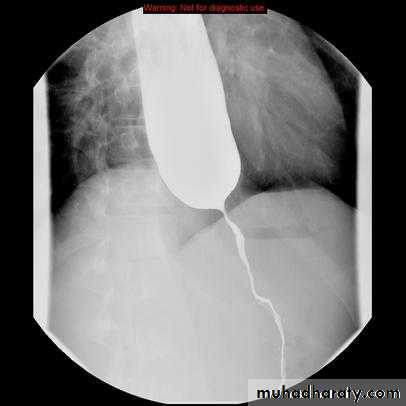

endoscopically:-a. forceful pneumatic dilatation using 30-35 mm diameter fluoroscopically positioned balloon across the gastro esophageal junction. It improves the symptoms in 80% of pt. we face two problems:-

Water soluble contrast swallows CT or OGD under GA.